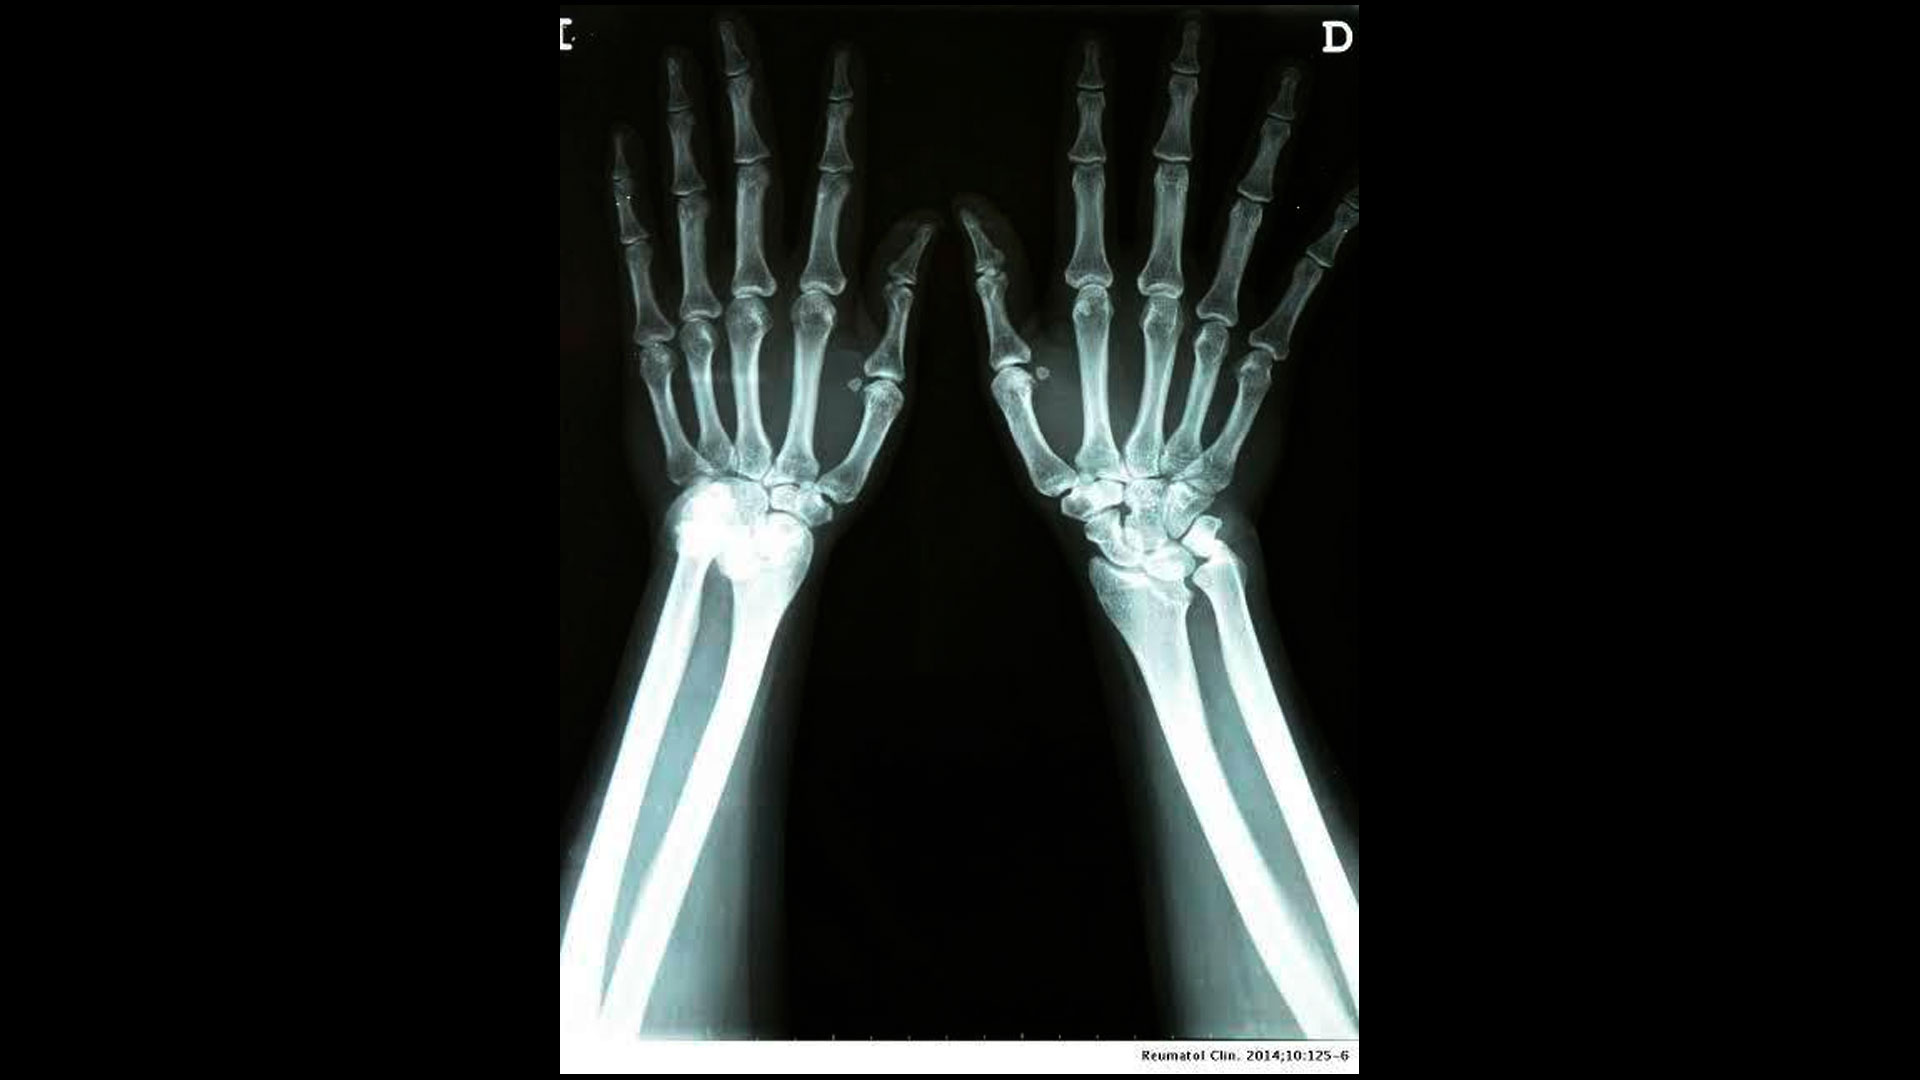

Diagnostics Free FullText Radiographic Findings of Inflammatory What Does White Mean On An X Ray  Your lungs, however, allow more radiation through. There is a large area of increased density on the left side of the chest. This has increased the density. The whiter the lungs appear on the scan, the more dense they. Your lungs look gray on. What Does White Mean On An X Ray.